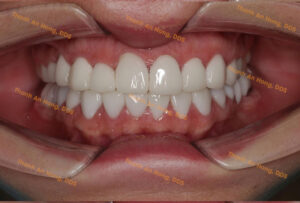

Khay trong suốt chỉnh lệch đường giữa với toàn hàm là răng sứ

Chỉnh khay giảm hô

Khay Chỉnh Hô Lùi Hàm – Không Nhổ Răng

Chỉnh móm với niềng khay trong suốt